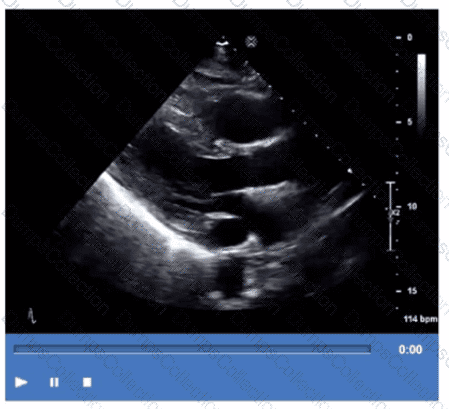

Which adjustment will improve the frame rate?